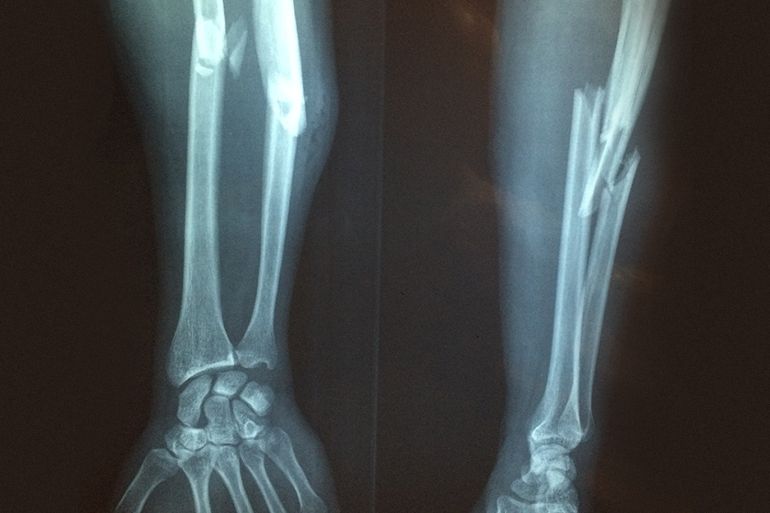

أوضح الدكتور أبو طربوش أن أكثر إصابات الأطفال شيوعا هي الكسور غير المزاحة أو قليلة الإزاحة، وعادة ما تكون في نهاية عظمة الكعبرة عند الرسغ، أو حول منطقة المرفق أي الكوع، بالإضافة لكسور الساق.